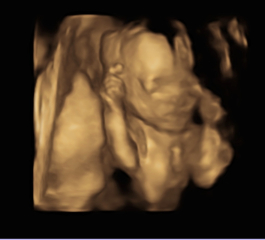

Had a private scan to see baby girl today as ive been so anxious! Everything was perfect and they did a small glampse of 4D! Look at her little fingers😍i feel like i can start to enjoy my pregnancy now that i know everything is okay!

Due March 2023 - thread 4

TeddyBeans · 18/10/2022 18:54

Katlouise24 · 18/10/2022 18:48

Beautiful pictures! 😍😍